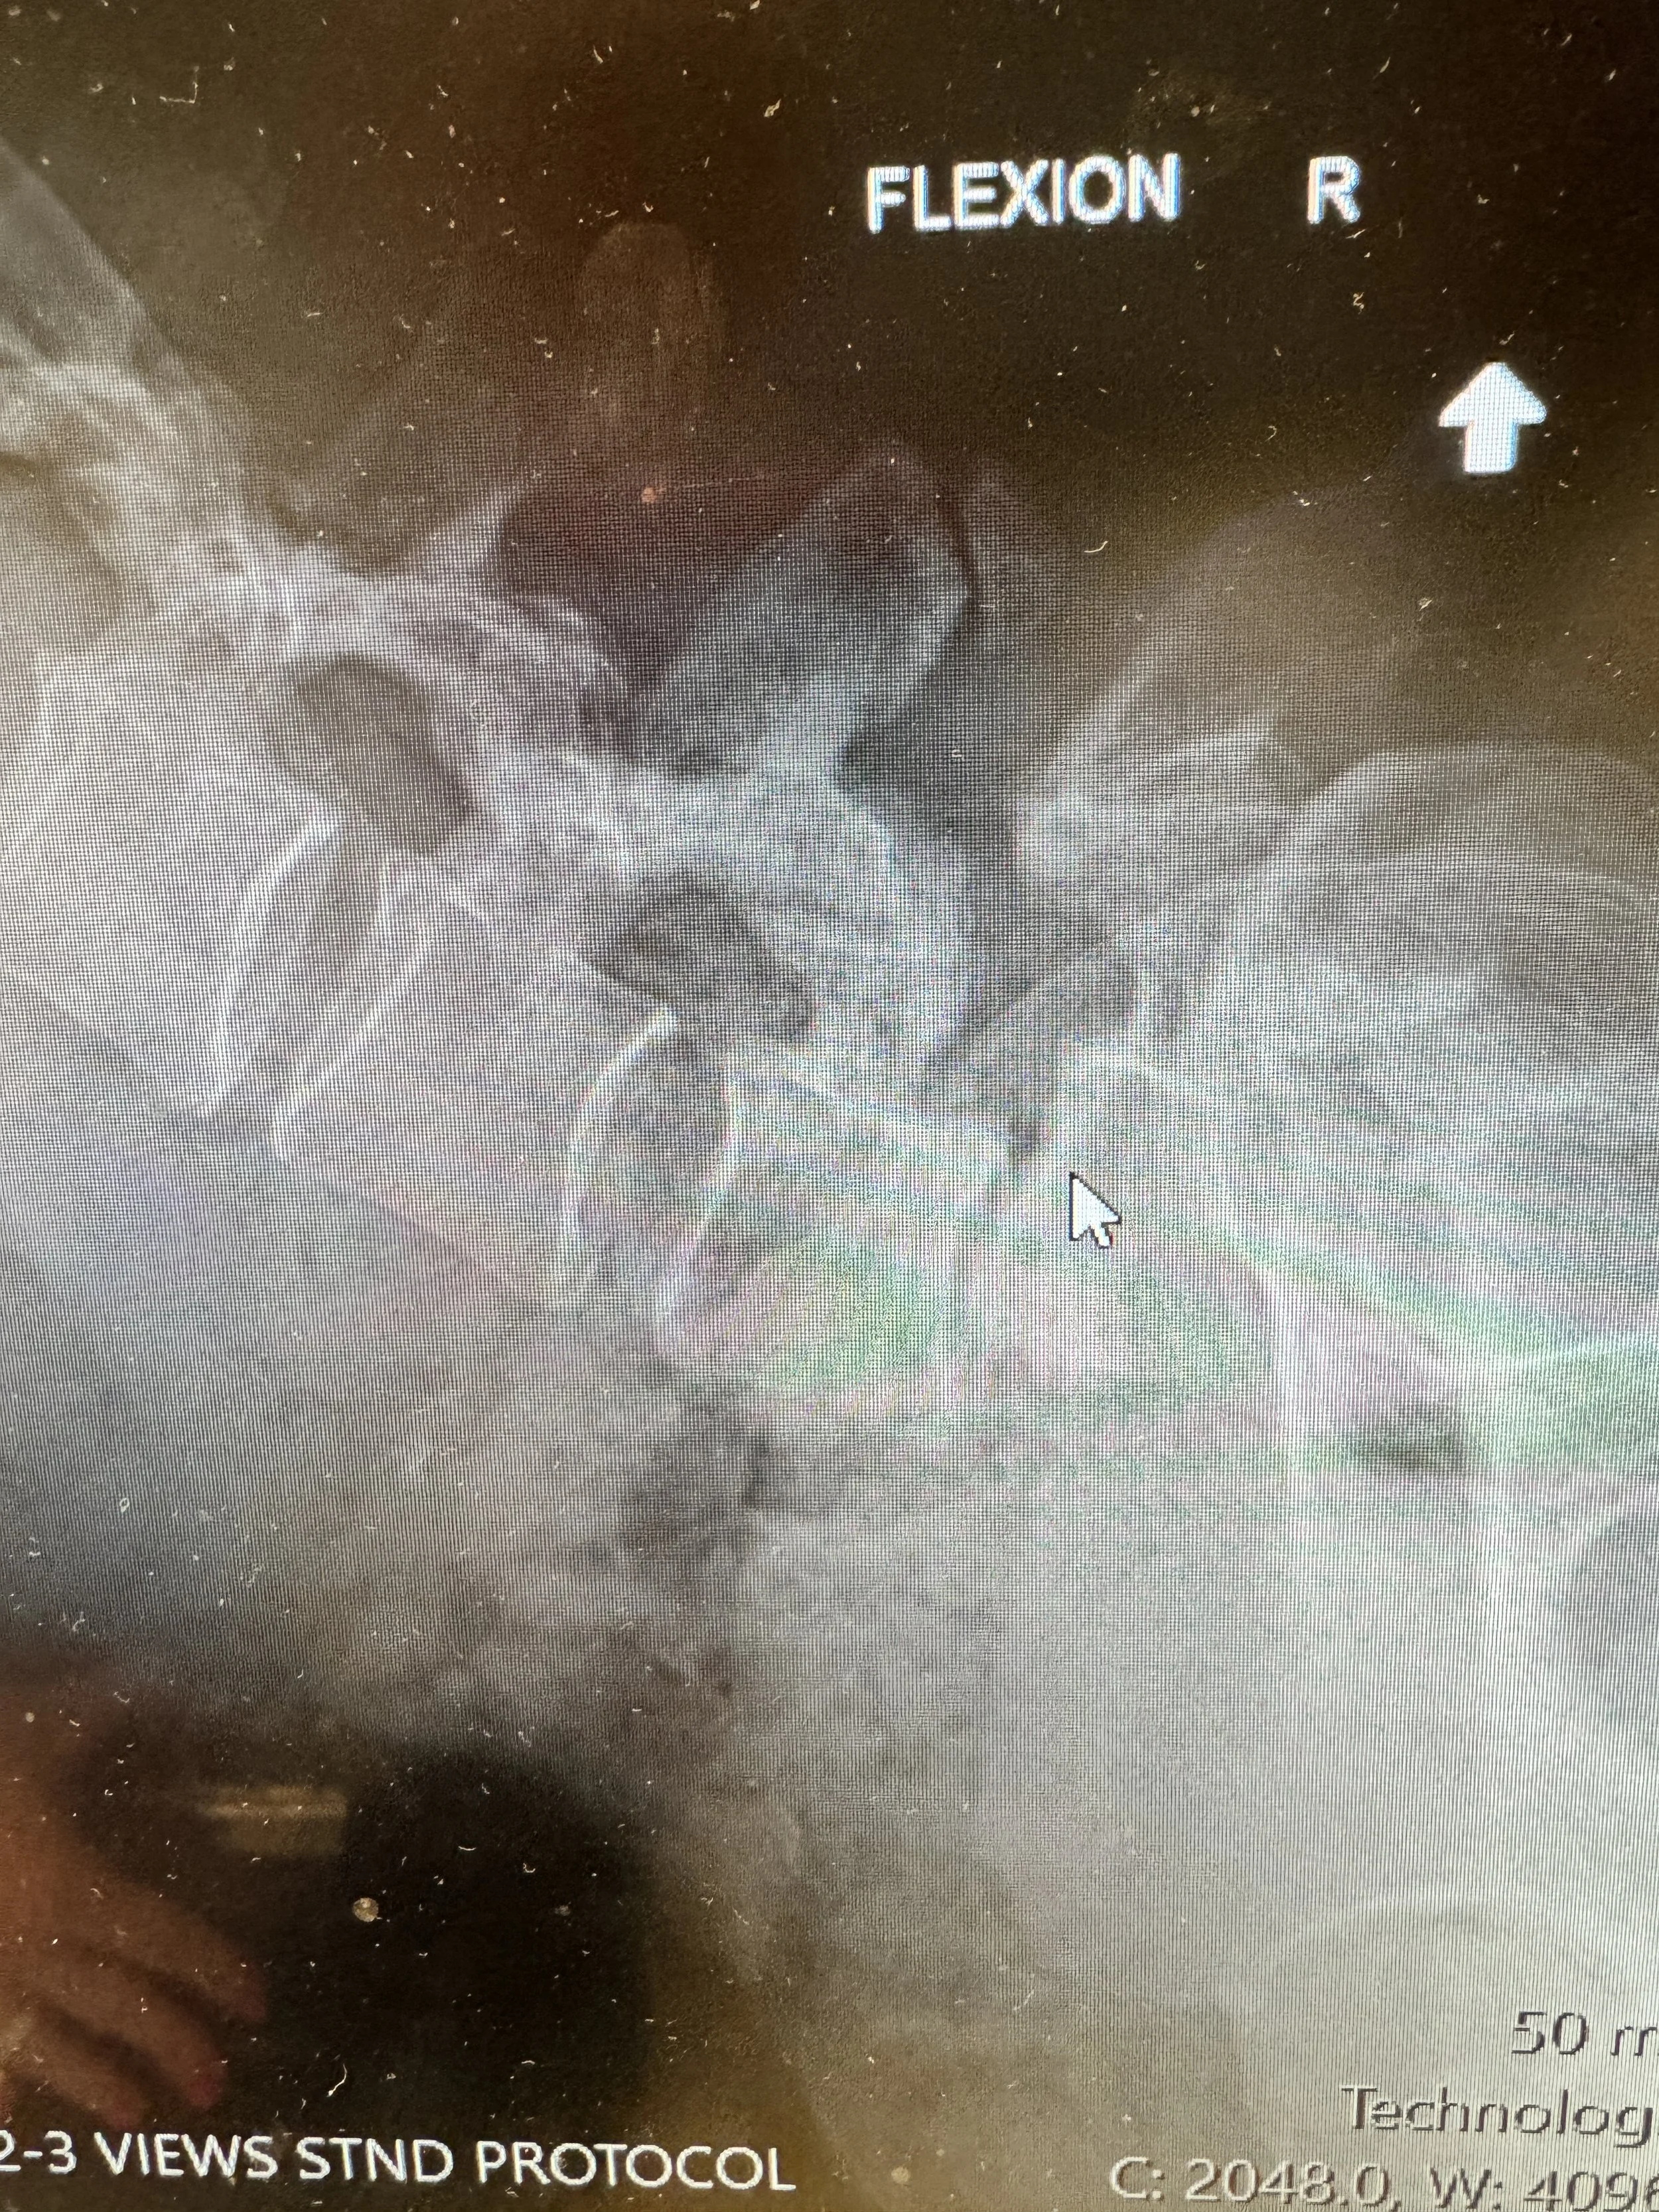

Spondylolysis is movement and misalignment of vertebrae. My L4 and L5 are naturally off by 9mm just standing. When I lean forward it shifts to nearly 15mm off and when I bend backwards it’s 3mm off. This movement without a disc creates bone on bone rubbing.